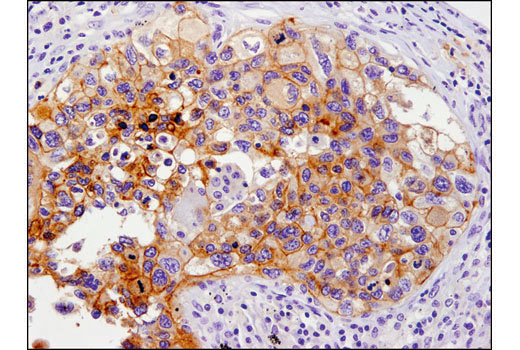

Immunohistochemical analysis of paraffin-embedded human lung carcinoma using PD-L1 (E1L3N®) XP® Rabbit mAb #13684.

In March 2022, AmoyDx received approval for the company’s PD-L1 Expression Detection Kit (IHC), which leverages the CST PD-L1 antibody validated for immunohistochemistry (IHC) and is used to guide the first-line treatment of Pembrolizumab in non-small cell lung cancer patients. With the expanded agreement in place, the companies will work together to identify additional antibody products against crucial targets that best support AmoyDx’s growing diagnostic portfolio, with a focus on enabling precision medicine for oncology therapeutics.